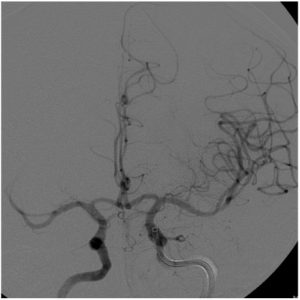

בחלק מהחולים ניתן לפתוח את העורק החסום בעזרת צנתור – העלאת צנתר מהמפשעה אל המוח, ( או כפי שד"ר רפאלי מבצע לעתים גם דרך היד) לתוך העורק המעורב תחת שיקוף רנטגן ובאמצעות שליפה מכנית של הקריש תחת שאיבת הקריש תחת מערכת יניקה בו-זמנית. שיטות אלו הוכחו בעשור האחרון כשיטות המובילות לשיפור במצבו הנוירולוגי וביכולת התפקוד העתידית של החולה ( עד 50% מהחולים).

טיפול פולשני: טיפול מחדֵש זרימה פולשני, על ידי צנתור מוחי, יתאים בדרך כלל לחולים שהפגיעה הנוירולוגית שלהם בעקבות השבץ חמורה יותר ובהתאמה חסימת עורק גדול ונגיש . צנתורי מוח לשבץ החלו באופן רשמי רק בעשור האחרון.

הצנתור נעשה תחת הרדמה כללית באמצעות שימוש בהתקן מכני (דמוי-רשת) מיוחד, שמוכנס לעורק החסום ושולף את הקריש החוצה או ע"י שאיבה בלחץ שלילי של הקריש, או שילוב של שתי השיטות.